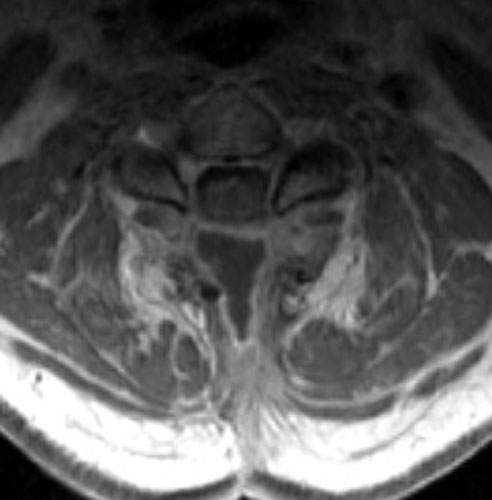

Seroma and Epidural Scar